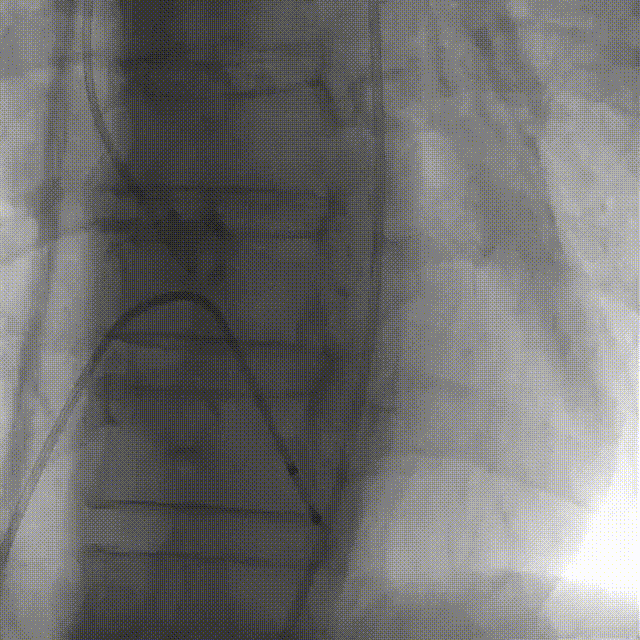

给予患者加强镇静后起搏下采用25mm球囊进行预扩张,无明显腰征,无瓣周漏。

球囊预扩

选用启明VenusA L29瓣膜,考虑Type0型二叶瓣的特殊狭窄情况选择稍高位释放,释放位置良好

瓣膜释放定位造影

瓣膜调整后释放造影

瓣膜释放完毕后,位置良好,但形态稍受挤压,采用25mm球囊进行后扩。